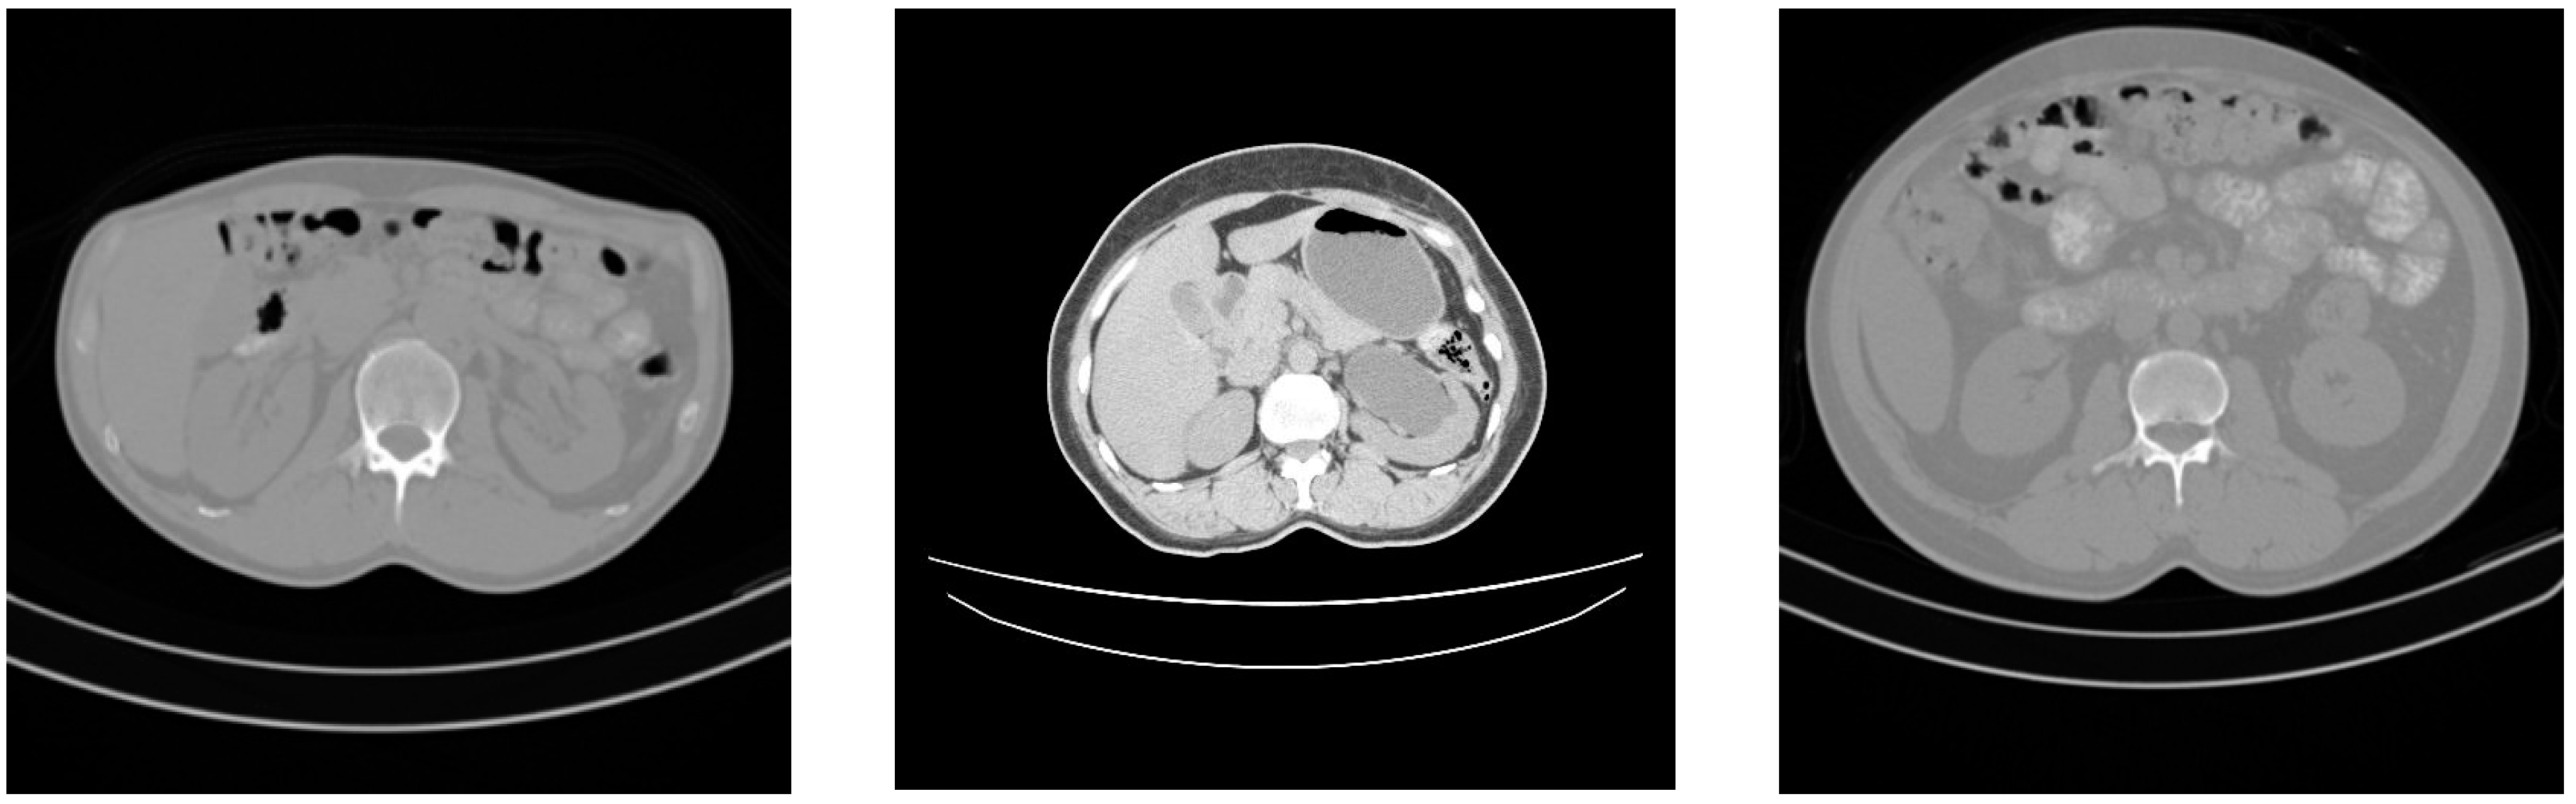

This prospective study included a total of 125 patients. The data set of 35 subjects (20 male subjects, 36 to 62 years old, mean age 49 years; 15 female subjects, 37 to 72 years old, mean age 51 years) was acquired using SIEMENS scanner at Country Heights Health Tourism Sdn. Bhd. Scanning was performed at 130 kV and 200 mA. The resolutions of the slices were 512 × 512 pixels, and the slice thickness was 2.5 mm in all subjects. The data set of the remaining subjects (57 male subjects, 24 to 72 years old, mean age 46 years; 33 female subjects, 26 to 70 years old, mean age 50 years) was acquired using a TOSHIBA scanner at the hospital of Serdang. Scanning was performed at 120 kV and 200 mA. The resolutions of the slices were 512 × 512 pixels, and the slice thickness was 2 mm or 3 mm. Both health centers are in the state of Selangor, Malaysia. The data set used is not publicly available due to the rights of Country Heights Health Tourism Sdn. Bhd and the hospital of Serdang located in Malaysia. Figure 1 shows some CT image samples from the employed data set.

Figure 1.

CT image samples.